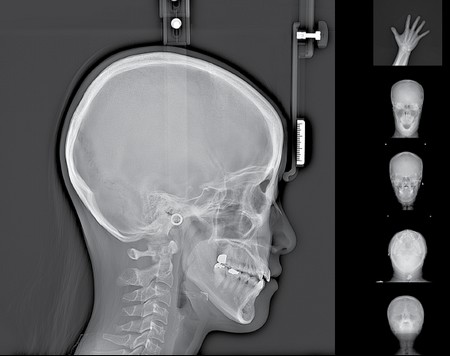

Rayscan a-SC (Alpha Pano Ceph) – панорамный рентгеновский аппарат последнего поколения с цефалостатом. Аппарат предназначен для панорамного сканирования зубов, челюстей и полости рта, а также включает в себя функцию сканирования для получения изображения головы. Специально разработанная конструкция аппарата позволяет в дальнейшем вне заводских условий произвести его дооснащение функцией компьютерной томографии (КТ). В стоимость аппарата входит мощный компьютер, программное обеспечение и беспроводной RF-пульт управления.

Ортопантомограф RAYSCAN является передовым диагностическим оборудованием, в котором применяются 2 сенсора: высококачественный плоский сенсор HAMAMATSU (Япония) для панорамной съёмки и отдельный сканирующий сенсор, которые обеспечивают чёткое изображение с первого раза (даже волос и мягких тканей), последний имеет различные режимы сканирования.

- Телерентгенографическое (ТРГ) сканирование: 5 режимов

Программное обеспечение Ceph:

- Превосходные инструменты для обработки и анализа изображений

- Полнопрофильный цефалометрический анализ боковой проекции

- Отслеживание и наложение изображений

- Интерфейс оптимизирован для стоматологического лечения.

- DICOM 3.0 совместимый формат.

- время сканирования: 2-14 сек, для цеф – 3,8-9,9 сек

- размер изображения: 150 мм макс для панорамы, 260х225 мм для цефалометрии